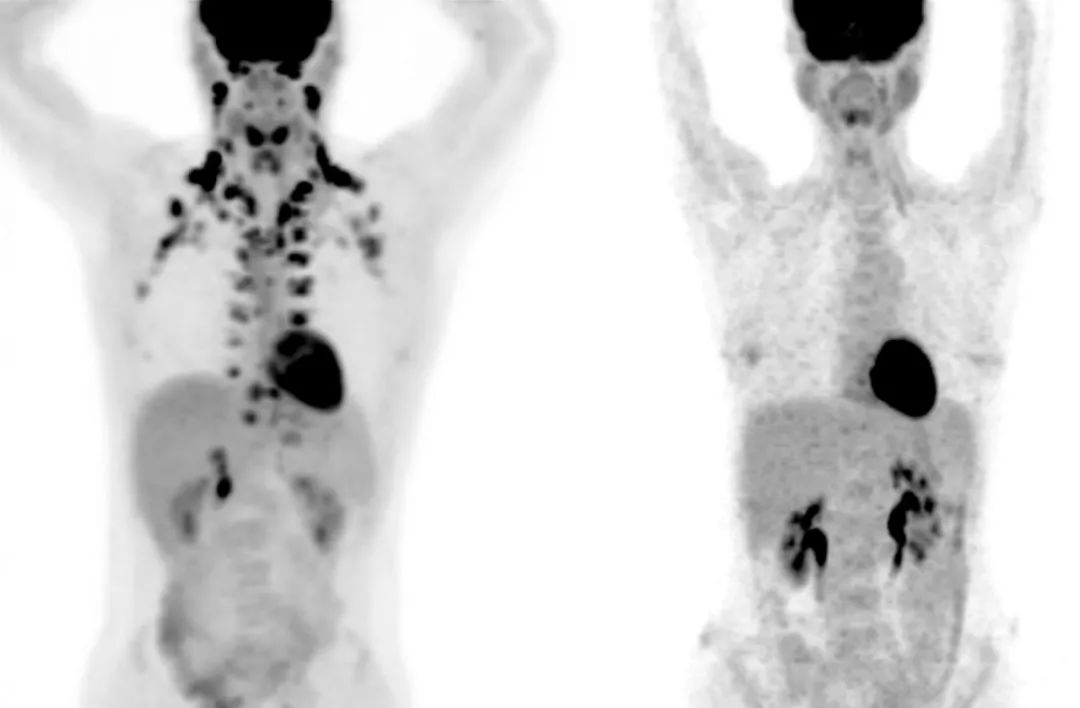

左图是颈部和锁骨部位有棕色脂肪的人,右图则没有(图片来源:MSKCC  Andreas G。 Wibmer & Heiko Schöder)左图是颈部和锁骨部位有棕色脂肪的人,右图则没有(图片来源:MSKCC  Andreas G。 Wibmer & Heiko Schöder)

但在之前,应该没有人能这么明确地得出上面的推断,毕竟成人身体存在BAT也是最近十几年才被研究证实的,2009年《新英格兰医学杂志》的研究确认,BAT是糖类和脂肪酸的代谢中心区域,且大多位于颈部和锁骨区域。在更早些时候,科学界认为BAT只存在于一些动物和人类婴儿体内,主要用来弥补年幼不发达的颤抖产热行为。而现在,BAT已经被定义成了一个重要的产热器官。

既然BAT可能存在这么多好处,怎么十多年来都没有人召集大量志愿者做一场双盲对照试验探索一下呢?原因恰好是要证明它们的存在,往往只能依赖正电子发射断层扫描(PET-Scan),这是一种常用于癌症治疗的技术。PET扫描原理并不复杂,机器检测由放射性示踪剂发射的辐射,再定位信号位置重建图像。

但扫描对象需要提前注射放射性示踪剂,即被放射性物质标记的生物物质,例如葡萄糖。这种放射性示踪剂被注入体内后,就能检测使用葡萄糖作为能量的细胞。一组细胞需要的能量越多,放射性示踪剂在该位置积累的越多,这对定位葡萄糖消耗量巨大的癌细胞很方便。不过,让健康的志愿者用PET来定位BAT显然存在很大的健康风险和生物伦理问题,许多研究便只能基于小鼠来进行操作。

Beche意识到,这里或许是一个真正有大量BAT样本数据的资源库。在与对方沟通合作过后,Beche拿到了病人的PET扫描数据,一共有超过5.2万名病人的13万张扫描图。根据记录,有BAT的PET扫描图占总数的5.9%,这些图来自5000多名病人,也就是大约10%的病人显示存在BAT。

为了验证PET数据的准确性,Beche特意将部分扫描图和电子计算机断层扫描(CT)图进行了比对,CT图显示存在脂肪的区域的确都能和PET图像的棕色脂肪对应上。当然研究者估计,由于这些病患都不是在寒冷环境中进行PET扫描的,实际有BAT的人数可能要更多。